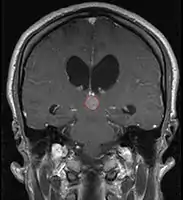

Pineal Gland Tumors

- Pineal parenchymal tumors (15-30%)

- Pineocytoma (WHO Grade II):

- Well-differentiated low grade tumor

- Characteristic pineocytomatous rosettes

- Pineoblastoma (WHO Grade IV):

- Primitive high grade tumor

- Believed to arise from an immature neural progenitor cells; may have pineal, neuronal, glial, or retinoblastic differentiation

- May be part of bilateral retinoblastoma with pineoblastoma syndrome ("trilateral retinoblastoma syndrome"), and may be associated with the Rb mutation

- Necrosis is common

- Histologically indistinguishable from Supratentorial PNET and infratentorial PNET (medulloblastoma)

- Similarly has a significant propensity for leptomeningeal spread